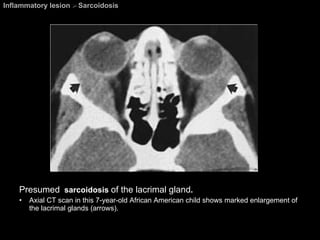

Inflammatory lesion  >  Sarcoidosis Presumed   sarcoidosis  of the lacrimal gland .  Axial CT scan in this 7-year-old African American child shows marked enlargement of the lacrimal glands (arrows).